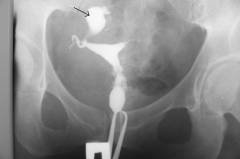

Радиография

Радиография представляет собой обычный рентгеновский снимок брюшной полости и полости таза. При массивном воспалительном процессе в области яичника образуется целый очаг. Расширенные сосуды переполняются жидкостью, часть из которой попадает в брюшную полость. Все это увеличивает плотность тканей в области воспалительного очага. Значительная часть рентгеновских лучей задерживается и на снимке видно патологическое образование. Данный метод обследования редко применяется в диагностике перекрута придатков матки из-за низкой информативности. Иногда к нему прибегают при отсутствии других способов визуализации проблемы.

Иногда применяется радиография с контрастом, когда в полость матки вводится специальное контрастное вещество. В норме оно проникает в маточные трубы и делает их хорошо различимыми на рентгеновском снимке. Если контраст не попал в маточную трубу, это может говорить о воспалении или перекруте трубы, в результате которого закрылся ее канал.